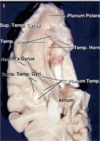

Key gyri on the lateral surface of the frontal lobe

Superior frontal gyrus

Middle frontal gyrus

Inferior frontal gyrus (pars triangularis, pars orbitalis, pars opercularis)

Precentral gyrus

Key sulci on lateral surface of frontal lobe

Superior frontal sulcus

Inferior frontal sulcus

Pre-central sulcus